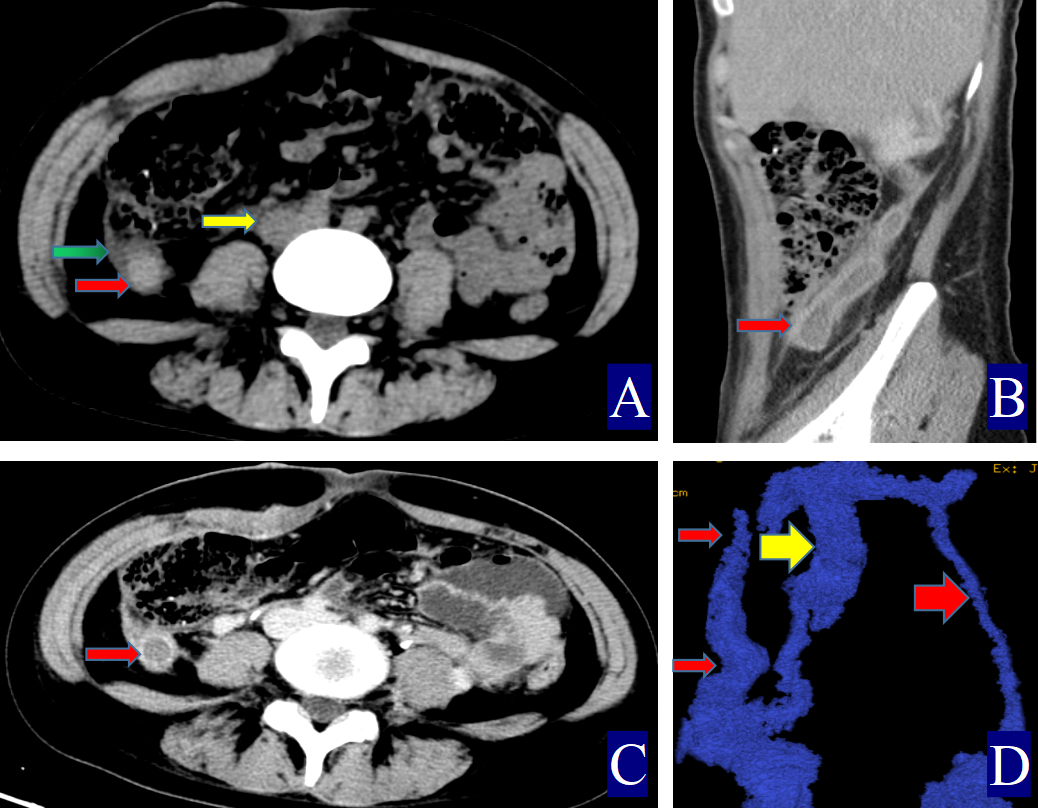

Fig. 2. A 17-year-old woman with left ovarian vein thrombophlebitis. The red color (red circle, red arrow and red cuboid) indicates the ovarian vein, the yellow color (yellow circle and yellow arrow) indicates the inferior vena cava. (A) Non-contrast axial CT image. The right OV measures approximately 0.91 cm in width (CT value = 46.10 HU, red arrow). The CT value of the inferior vena cava is 32.00 HU (yellow arrow). (B) Non-contrast coronal CT image showing the left OV (red arrow). (C) Contrast-enhanced axial CT image. Thrombosis in the left OV with uniform wall thickening (red arrow). (D) Contrast-enhanced coronal CT image. Left POVT with uniformly thickened wall (red arrow).

The primary CT findings of POVT included filling defects within the ovarian vein lumen along with thickening of the vessel wall (Figs. 1,2,3). Secondary signs involved pelvic effusion in 13 cases and periovarian venous exudation with increased fat density in 19 cases (Figs. 1A,C,3A,C). One patient, who developed extensive thrombosis extending to both lower extremity veins, the inferior vena cava, and pulmonary arteries, died from postpartum hemorrhagic shock. The remaining 23 patients fully recovered.

Compared with the non-POVT group, the POVT group showed significantly greater ovarian vein width on the thrombus side, higher CT attenuation of the thrombus-side ovarian vein, as well as increased CT attenuation difference and ratios (p = 0.001, Figs. 1,2,3). Using 0.90 cm as the cut-off value for ovarian vein width, the sensitivity reached approximately 91.70%, with a specificity of 95.20% (Figs. 1A,2A,3A,C,D). With 46.00 HU as the threshold for ovarian vein CT value on the thrombus side, both sensitivity and specificity were 100% (Figs. 1A,2A,3A). For a CT attenuation difference cut-off of 12.50 HU, the sensitivity was 95.30%, and specificity remained 100%. Similarly, a ratio cut-off of 1.1 yielded a sensitivity of 95.30% and specificity of 100% (Figs. 1A,2A,3A).

Direct signs observed on CT included variable widening of the ovarian vein, increased intraluminal density, and filling defects, often accompanied by vessel wall thickening, which is in line with prior reports [16, 17, 18, 19, 20, 21] (Figs. 1,2,3). A notable finding in our study was the identification of previously undescribed indirect signs: increased fat density around the ovarian vein in the pelvis and the presence of small-volume pelvic effusion (Figs. 1A,3A–D). These signs may reflect the local inflammatory reaction associated with thrombophlebitis.

Semi-quantitative parameters from non-contrast CT scans revealed clear differences between the POVT and non-POVT groups. The thrombus-side ovarian vein width, CT attenuation of the thrombotic ovarian vein, the difference between ovarian and inferior vena cava CT values, and their ratio were all significantly higher in the POVT group (p = 0.001, Figs. 1,2,3). These parameters may serve as reliable diagnostic references. For instance, using 0.90 cm as the cut-off for ovarian vein width yielded a sensitivity of approximately 91.70% and a specificity of 95.20%. This supports earlier findings [5] that vein enlargement is a key feature of POVT (Figs. 1,2,3). A CT attenuation cut-off of 46.00 HU for the thrombotic ovarian vein achieved 100% sensitivity and 100% specificity (Figs. 1,2,3). Similarly, a CT attenuation difference threshold of 12.50 HU and a ratio cut-off of 1.1 also demonstrated strong diagnostic performance (Figs. 1,2,3). However, in one patient with extensive thrombosis of the inferior vena cava, the ovarian vein had a lower CT value than the cava, resulting in a negative difference (–12.50 HU) and a ratio of 0.83, reflecting variability in advanced or complex cases. Currently available non-invasive diagnostic tools for POVT include Doppler ultrasound (sensitivity 52%), magnetic resonance imaging (MRI) (92%), and contrast-enhanced multidetector CT (100%) [5]. The present study indicates that non-contrast CT semi-quantitative parameters can closely match the diagnostic accuracy of enhanced CT, while offering greater simplicity, lower cost, and avoiding the risks associated with contrast agent use.